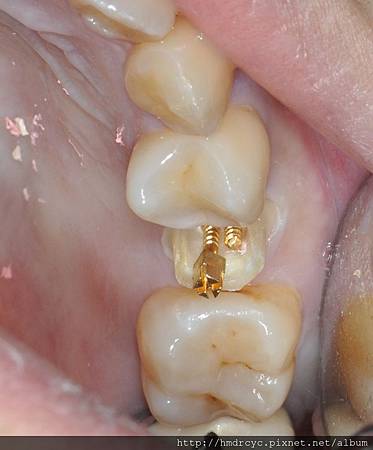

在全瓷牙使用石英鑄心與玻璃纖維鑄心

有金屬的傳統瓷牙則使用螺旋鑄心

鎖上裝置好後 加上樹脂填補恢復牙齒結構

後續的假牙裝置如一般牙齒